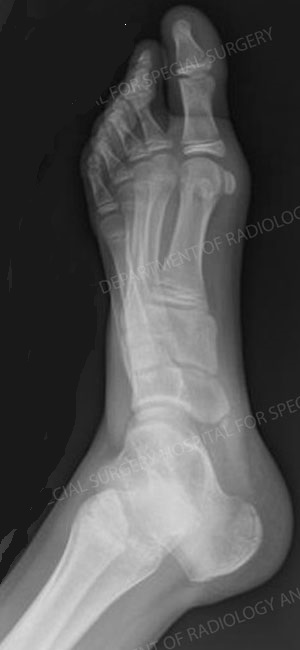

All sort of treatment and modalities available for sport injuries with the help of physiotherapy early rehabilitation of the injured person possible for easy and fast recovary all sort of ligament repair done here arthroscopic and minimal invasive surgeries available intraarticular injections imported plasters all available

Hand injuries are very common in industrial workers.

We provide treatment for all kind of hand injuries. It includes :